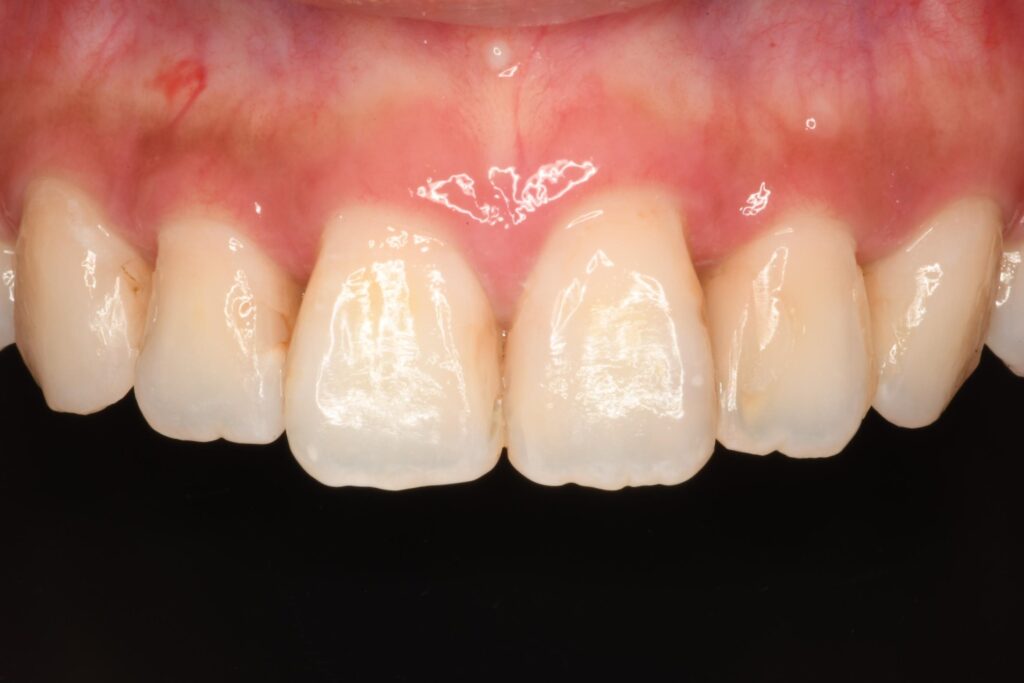

【治療ブログ】前歯の見た目が気になる…コンポジットレジンで自然に改善しました【保険診療】

「前歯の見た目が気になって…」というご相談で来院された患者さん。 鏡を見るたびに気になってしまう前歯の形…